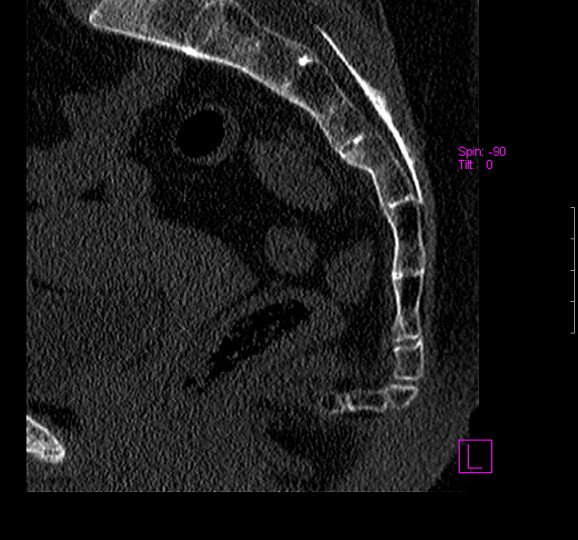

При подозрении на вывих необходимо обратиться к травматологу. Для диагностики используются следующие методы:

- При сложной патологии назначаются МРТ и рентген, которые помогают уточнить степень повреждения.